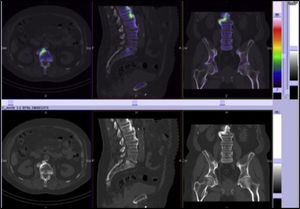

In the bone scan images there was no sign of articular pathological uptake (Fig. 3). Multimodality SPECT/CT tomographic images were then acquired (Figs. 4 and 5), which were used both for qualitative visual analysis of the sacroiliac joint, and for quantitative analysis which permitted the obtainment of indicators of the sacroiliac-promontory. In visual analysis calcification of the anterior common vertebral ligament was detected, together with absence of sacroiliac uptake. With this information and inferior promontory-sacroiliac indicators below the established cut-off level for diagnosis of sacroiliitis, diagnosis of ankylosing spondylitis was excluded, with support for the diagnosis of Forestier's disease.

SPECT/CT slice images in axial, sagittal and coronal planes with low uptake of the radiopharmaceutical in sacroiliac joints. Sacroiliac/promontory values below cut-off level established for diagnosis of sacroiliitis.7,8